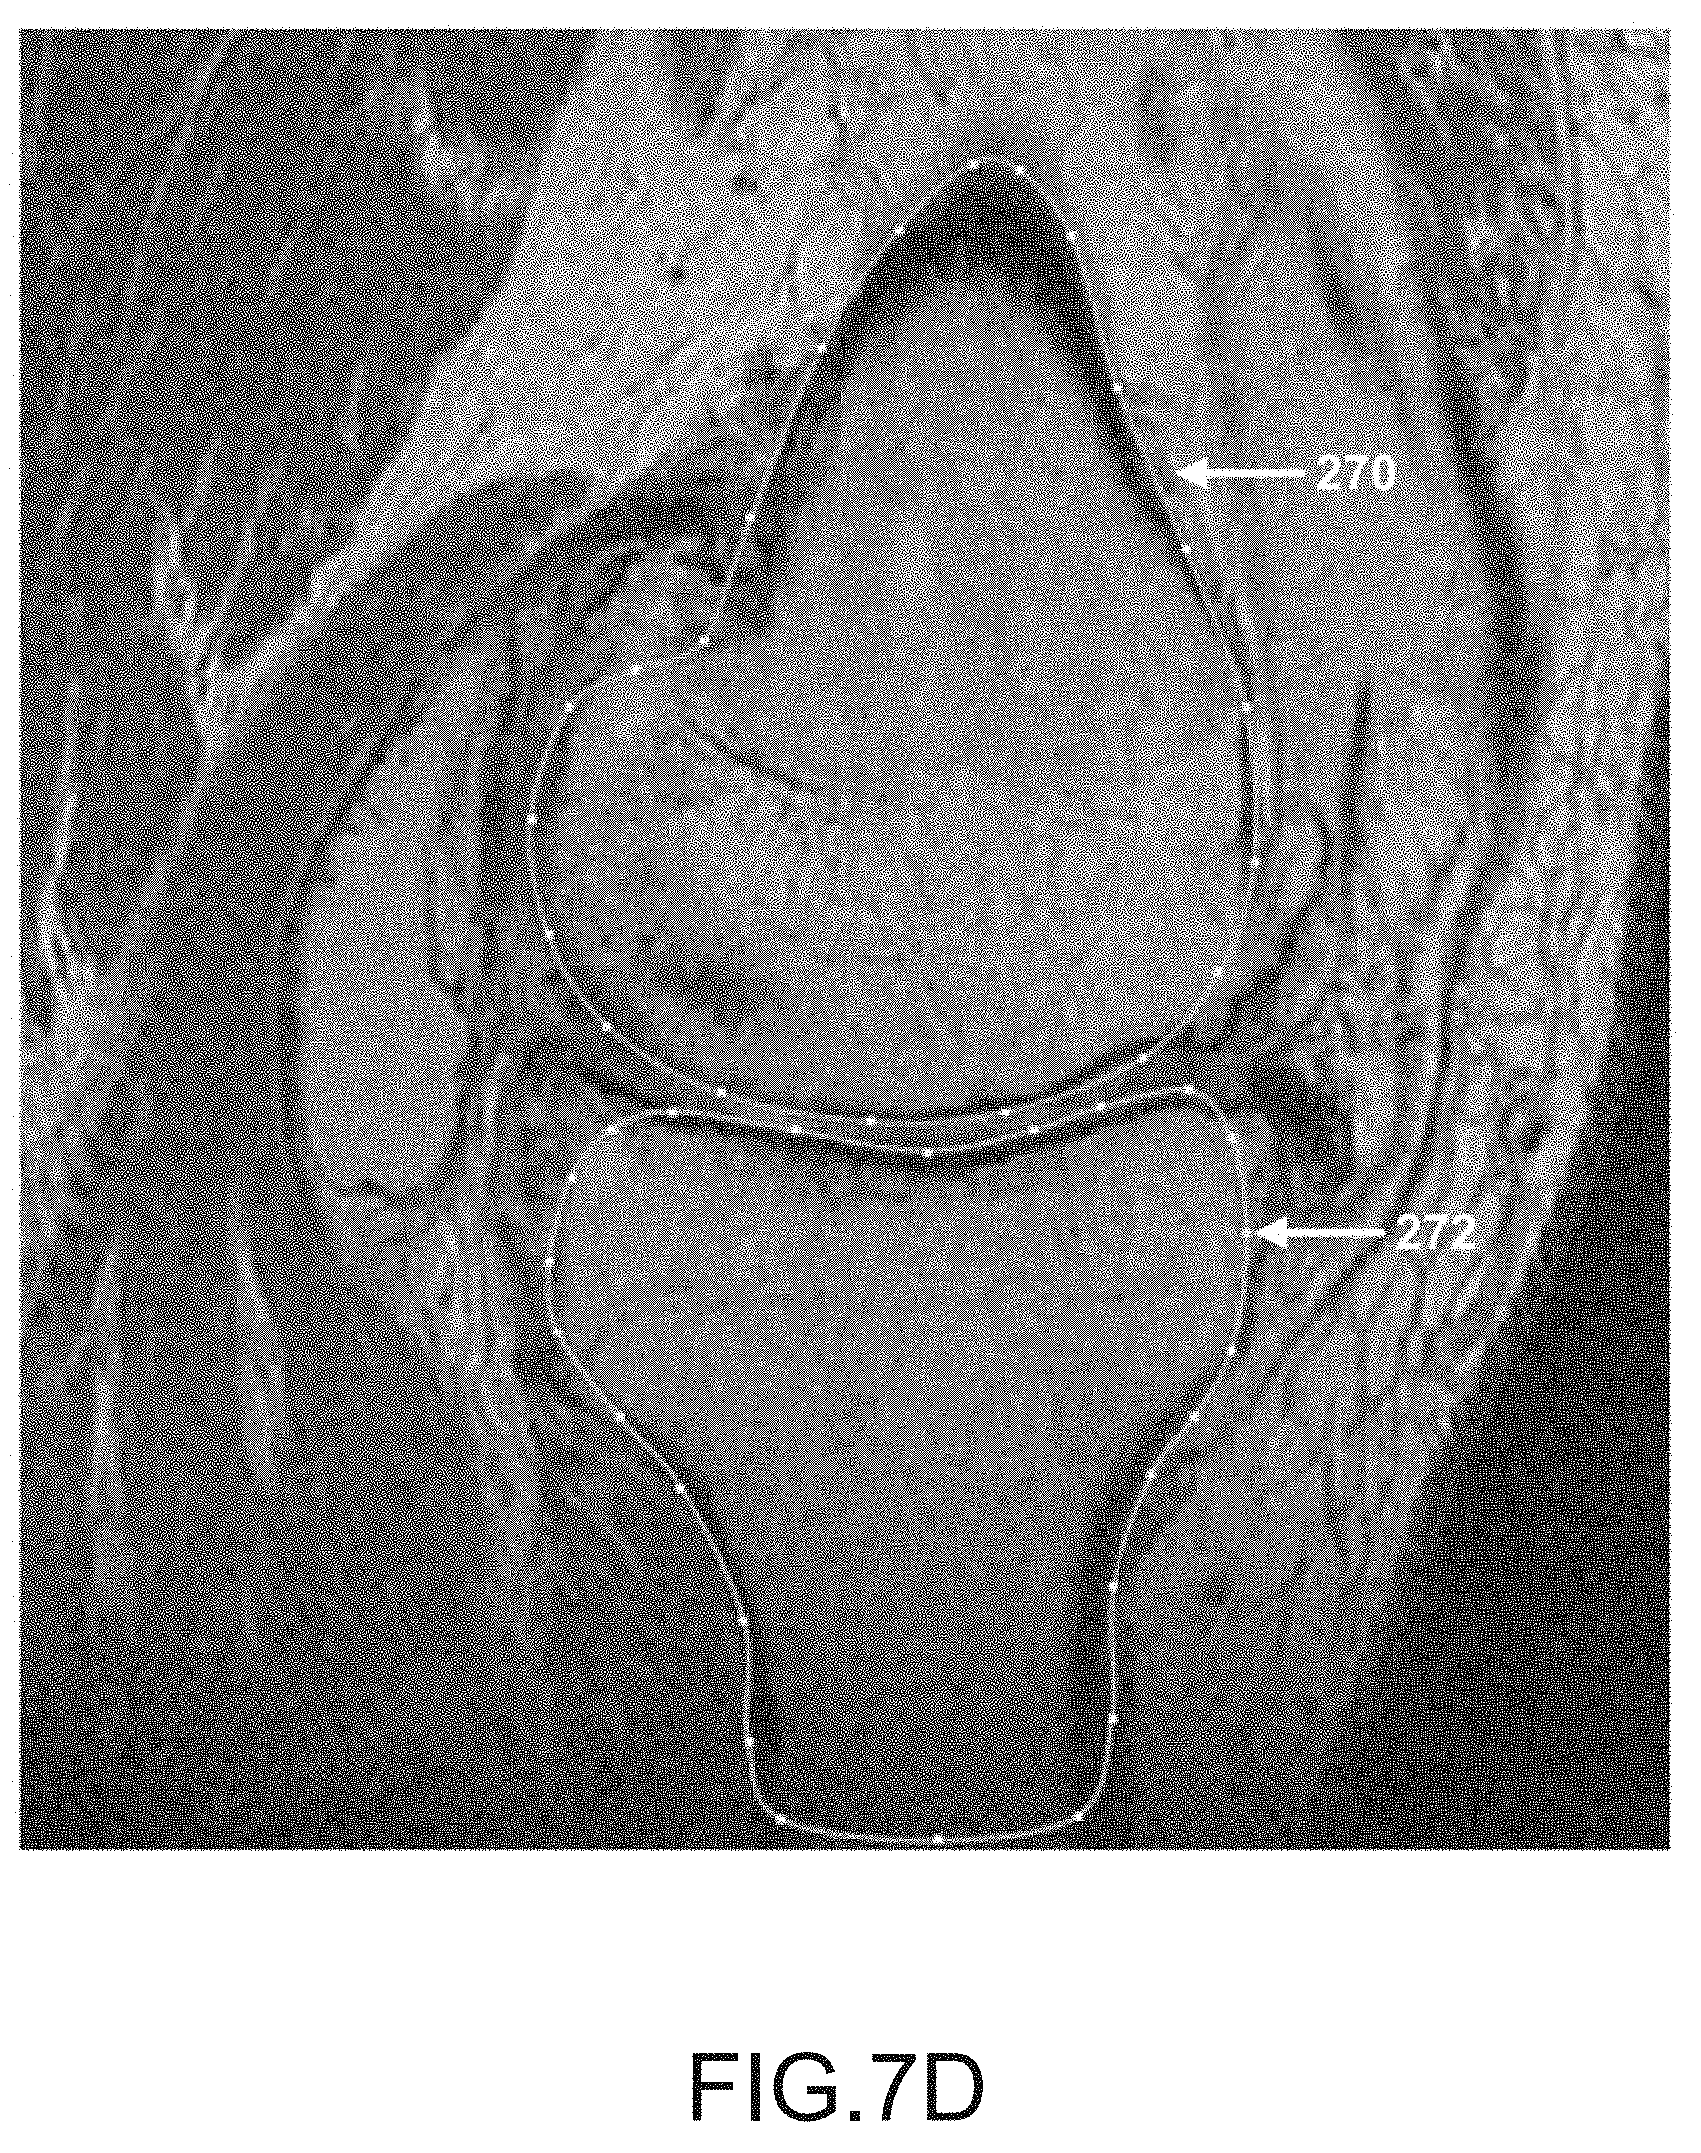

[0053]

FIG. 7D is another sagittal plane image slice of a segmented femur and tibia.

After operation 250 obtains scan data (e.g., scan images 16) generated by imager 8, operation 252 may be performed to segment the femur data of the scan data. During this operation, the femur may be located and spline curves 270 may be generated to outline the femur shape or contour lines in the scan slices, as depicted in FIGS. 7A-7K. It should be appreciated that one or more spline curves may be generated in each slice to outline the femur contour depending on the shape and curvature of the femur as well as the femur orientation relative to the slice direction.

[0165]

After operation 256, operation 258 may be performed to segment the tibia data in the scan data. During this operation, the tibia is located and spline curves may be generated to locate and outline the shape of the tibia found in the scan slices, as depicted by tibia spline curves 272 in FIGS. 7A-7K. It should be appreciated that one or more spline curves may be generated in each slice to outline the tibia depending on the shape and curvature of the tibia as well as the tibia orientation relative to the slice direction.